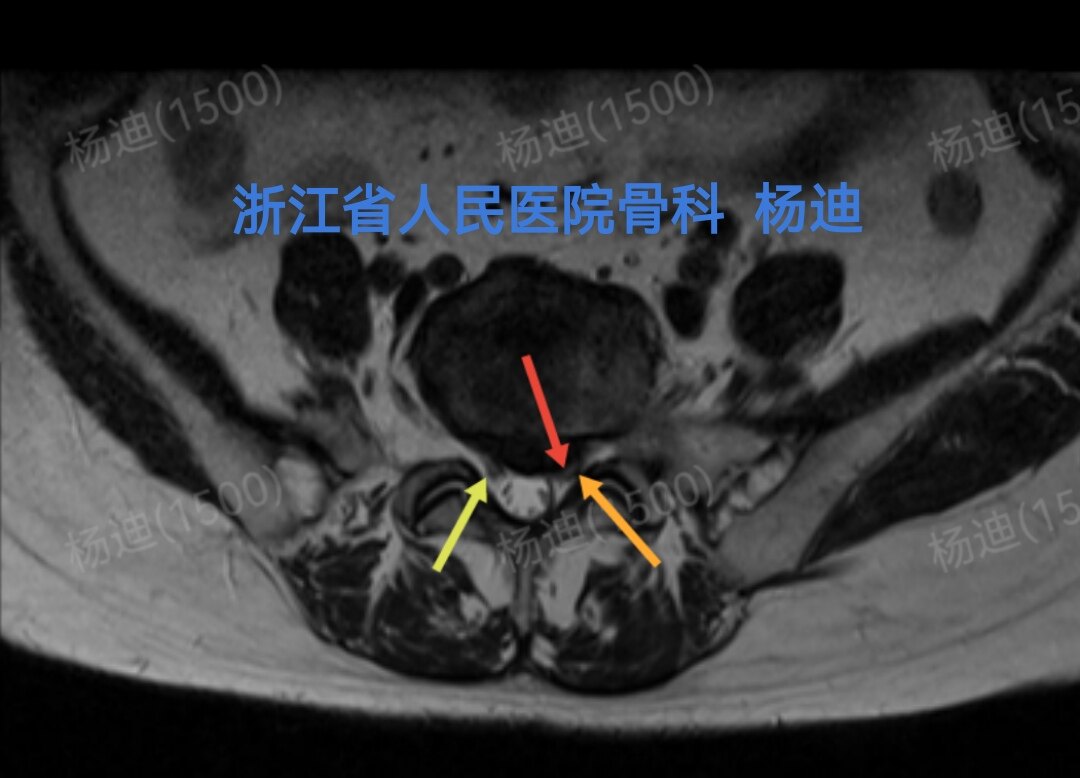

图为磁共振横断面检查:腰5/骶1椎间盘突出(红箭头),左神经根受压(橙箭头),右神经根松弛(黄箭头)